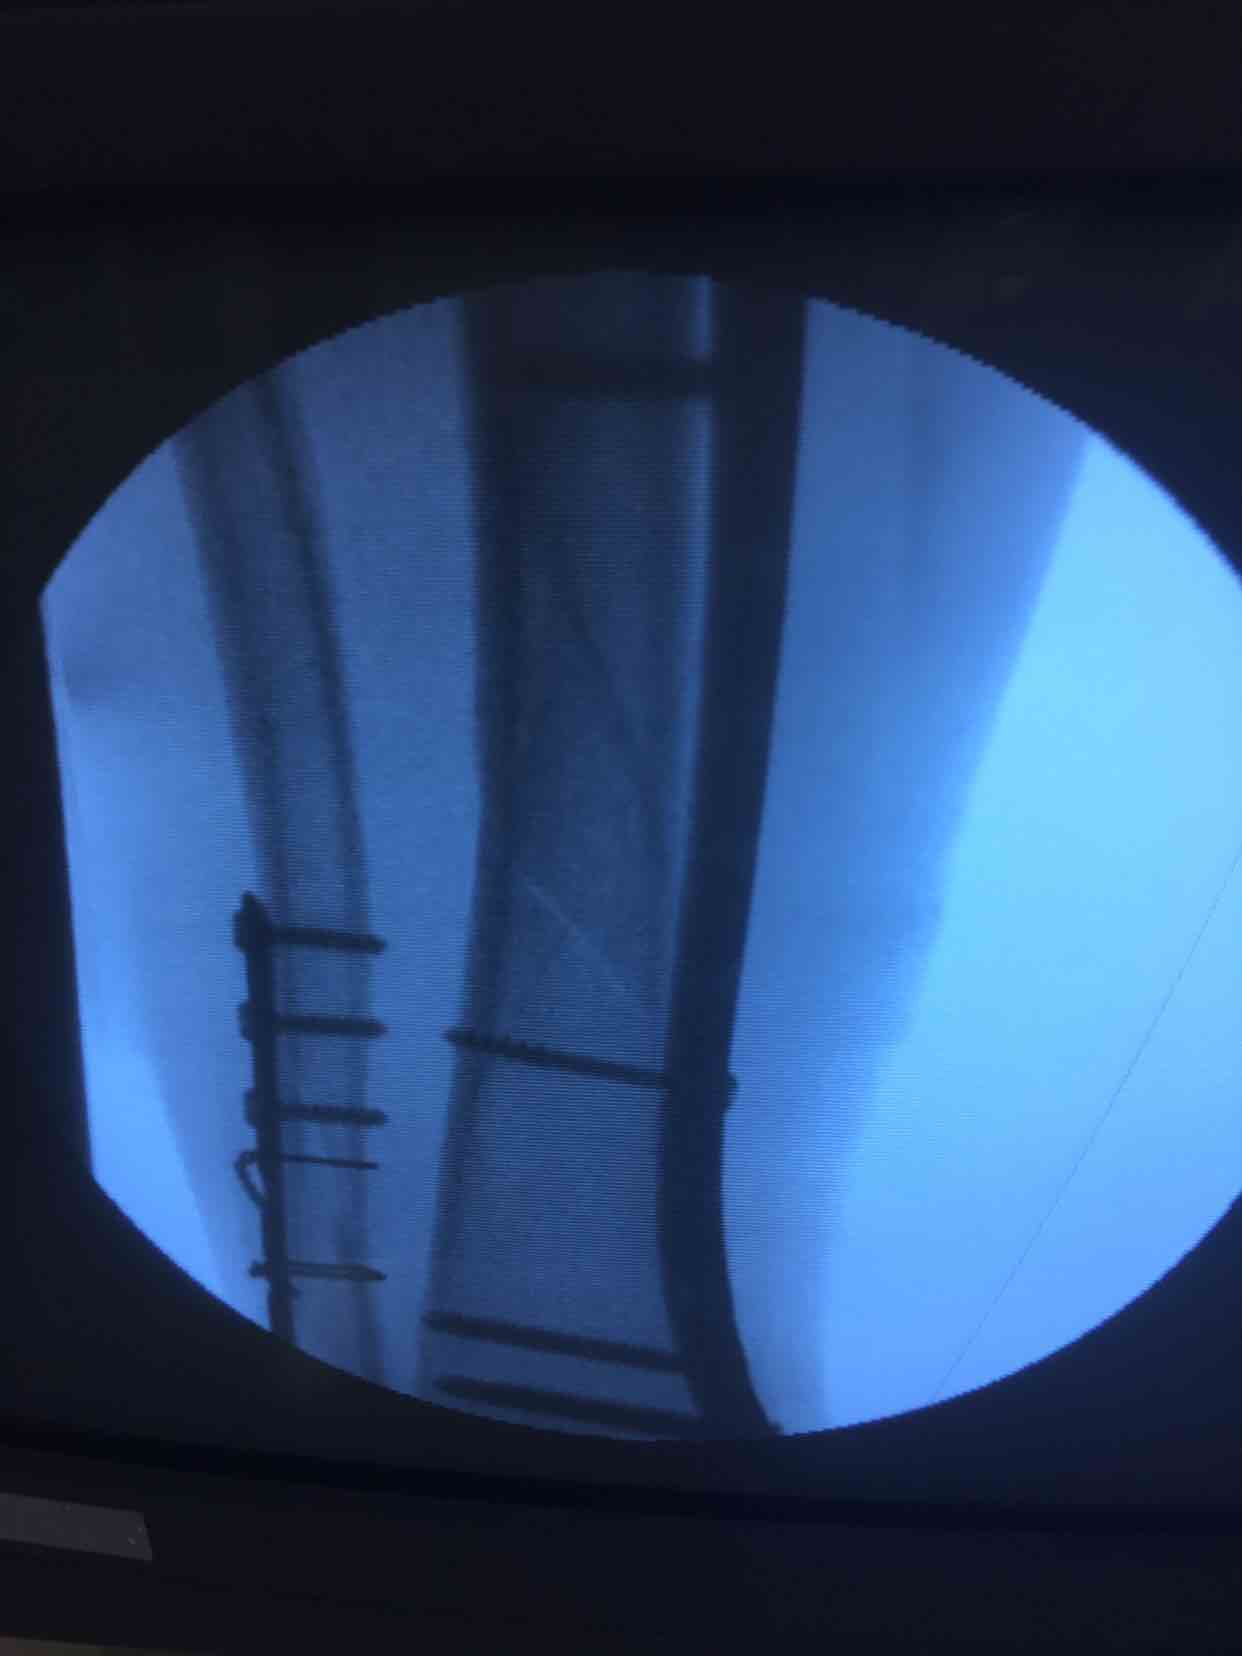

在腰麻下行切开复位内固定术,术后抗炎,消肿等处理。

- 高兵回复导火索:手术方式选择决定术后愈合情况,微创最大优势就是软组织保护,骨折早日愈合。